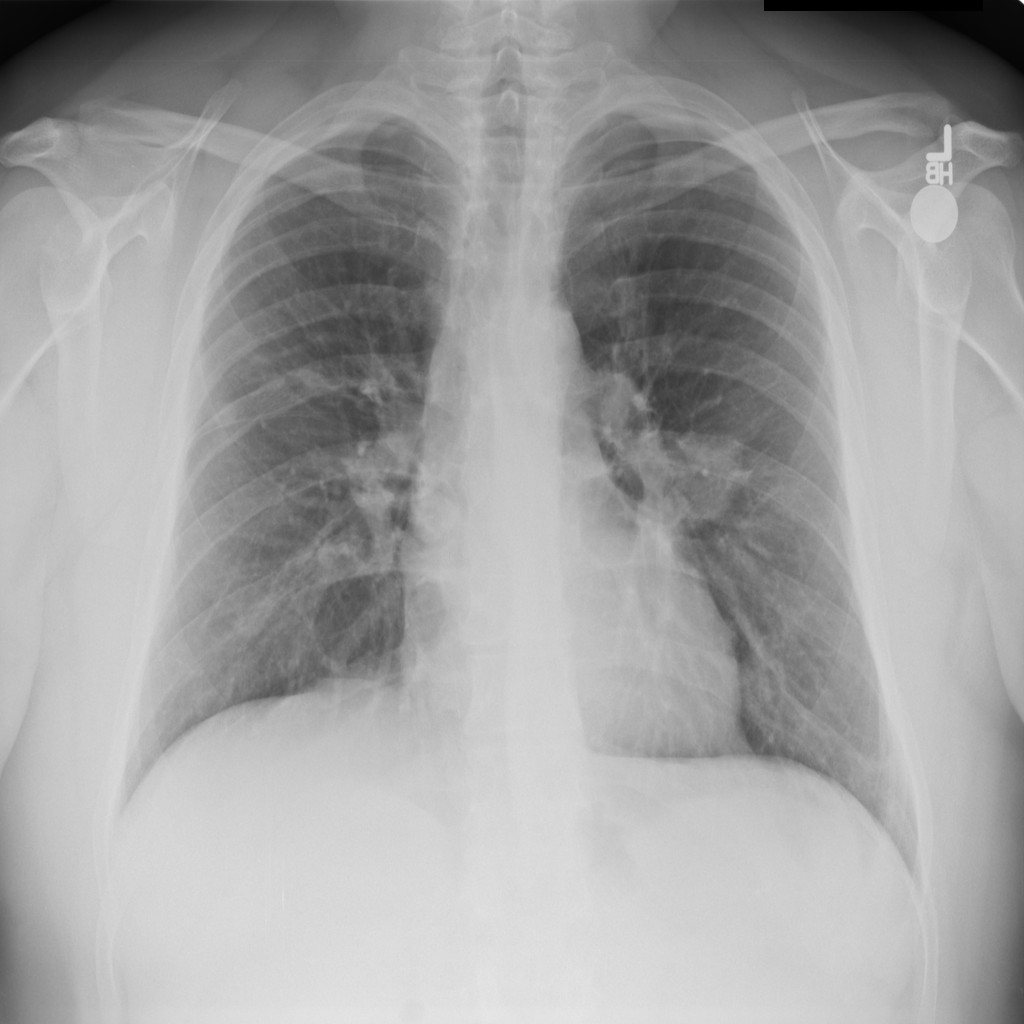

Showing up to 90 reference images for Pneumonia.

PAT-B3C3 · IMG-001Pneumonia

PAT-B3C3 · IMG-001

PA